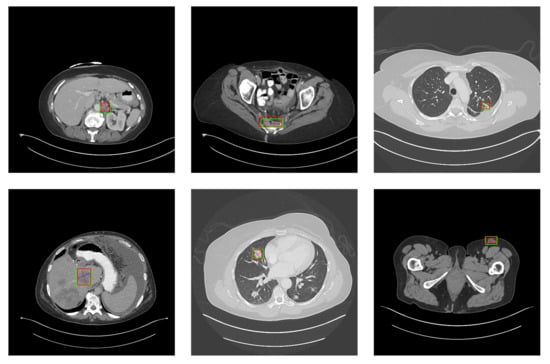

5.2. Detection Results

For further comparison, we extracted six images from the CT image series of DeepLesion. These images were taken from different sites of lesions and different areas of lesions, showing the detection results of the comparison model as comprehensively as possible. Figure 10, Figure 11, Figure 12, Figure 13, Figure 14, Figure 15, Figure 16, Figure 17, Figure 18 and Figure 19 show the detection results. All green boxes represent ground truth; red boxes denote predicted bounding boxes. It can be seen that Faster-RCNN performs very poorly on small lesions and lesions that are not easy to identify, while YOLO v3, YOLO v4, and SSD series perform relatively well. However, the aspect regression of the bounding box at small lesion locations is still not accurate. On the other hand, EfficientDet, Mask-RCNN, and YOLO v5 perform relatively well and detect lesions accurately. This may be related to the attention extraction module in these networks.

The detection results of YOLO v3 in the DeepLesion dataset. The green box marks the location of the lesion.

Figure 11.